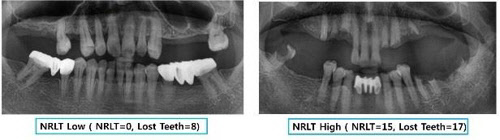

빠진 치아를 대부분 재건한 영상(왼쪽)과 재건하지 않고 방치한 영상(오른쪽)

논문을 보면 빠진 치아를 재건하지 않은 개수가 5개 이상으로 많은 노인은 4개 미만인 노인보다 인지장애위험이 2.74배 더 높은 것으로 평가됐다. 치아 상실 자체는 인지기능 장애의 위험 요인은 아니었으나, 빠진 치아를 재건하지 않고 방치하는 경우는 인지기능 장애의 위험 요인이었다.

흥미로운 건 자연치아가 16개 남아있으면서 재건하지 않은 상실 치아가 5개 이상인 사람은 인지장애 위험이 최대 4.36배에 달했지만, 자연치아가 7개로 적으면서도 상실 치아를 4개 미만으로 남겨두고 나머지 치아 전체를 의치로 재건한 사람에서는 인지장애 위험이 관찰되지 않았다는 점이다.